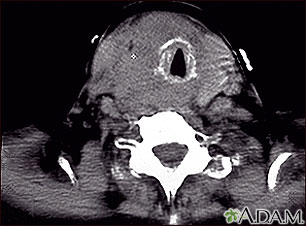

- CT scan of the neck or MRI to determine the size of the tumor.